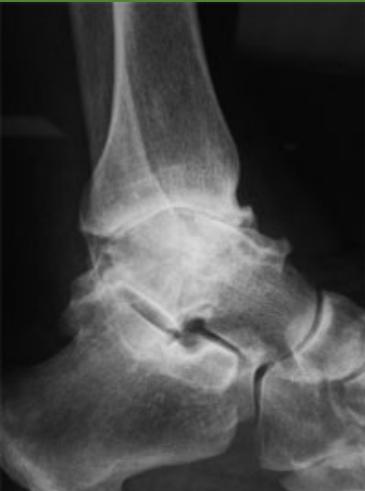

| K-wire (Kirschner Wire) | Indications: Pediatric fractures, small bone fractures in adults. Advantages: Easy to apply/remove. Disadvantages: Not stable alone, risk of infection. | , , , , , ![]() |

| Tension-band Wires | Indications: Patellar and olecranon fractures, possible in malleolar fractures. Application involves K-wires as a base. | , , , , ![]() |

| Screw Types - Cannulated Screws | Feature: Hollow, inserted over a wire for accurate placement in minimally invasive techniques. | , , , , ![]() |